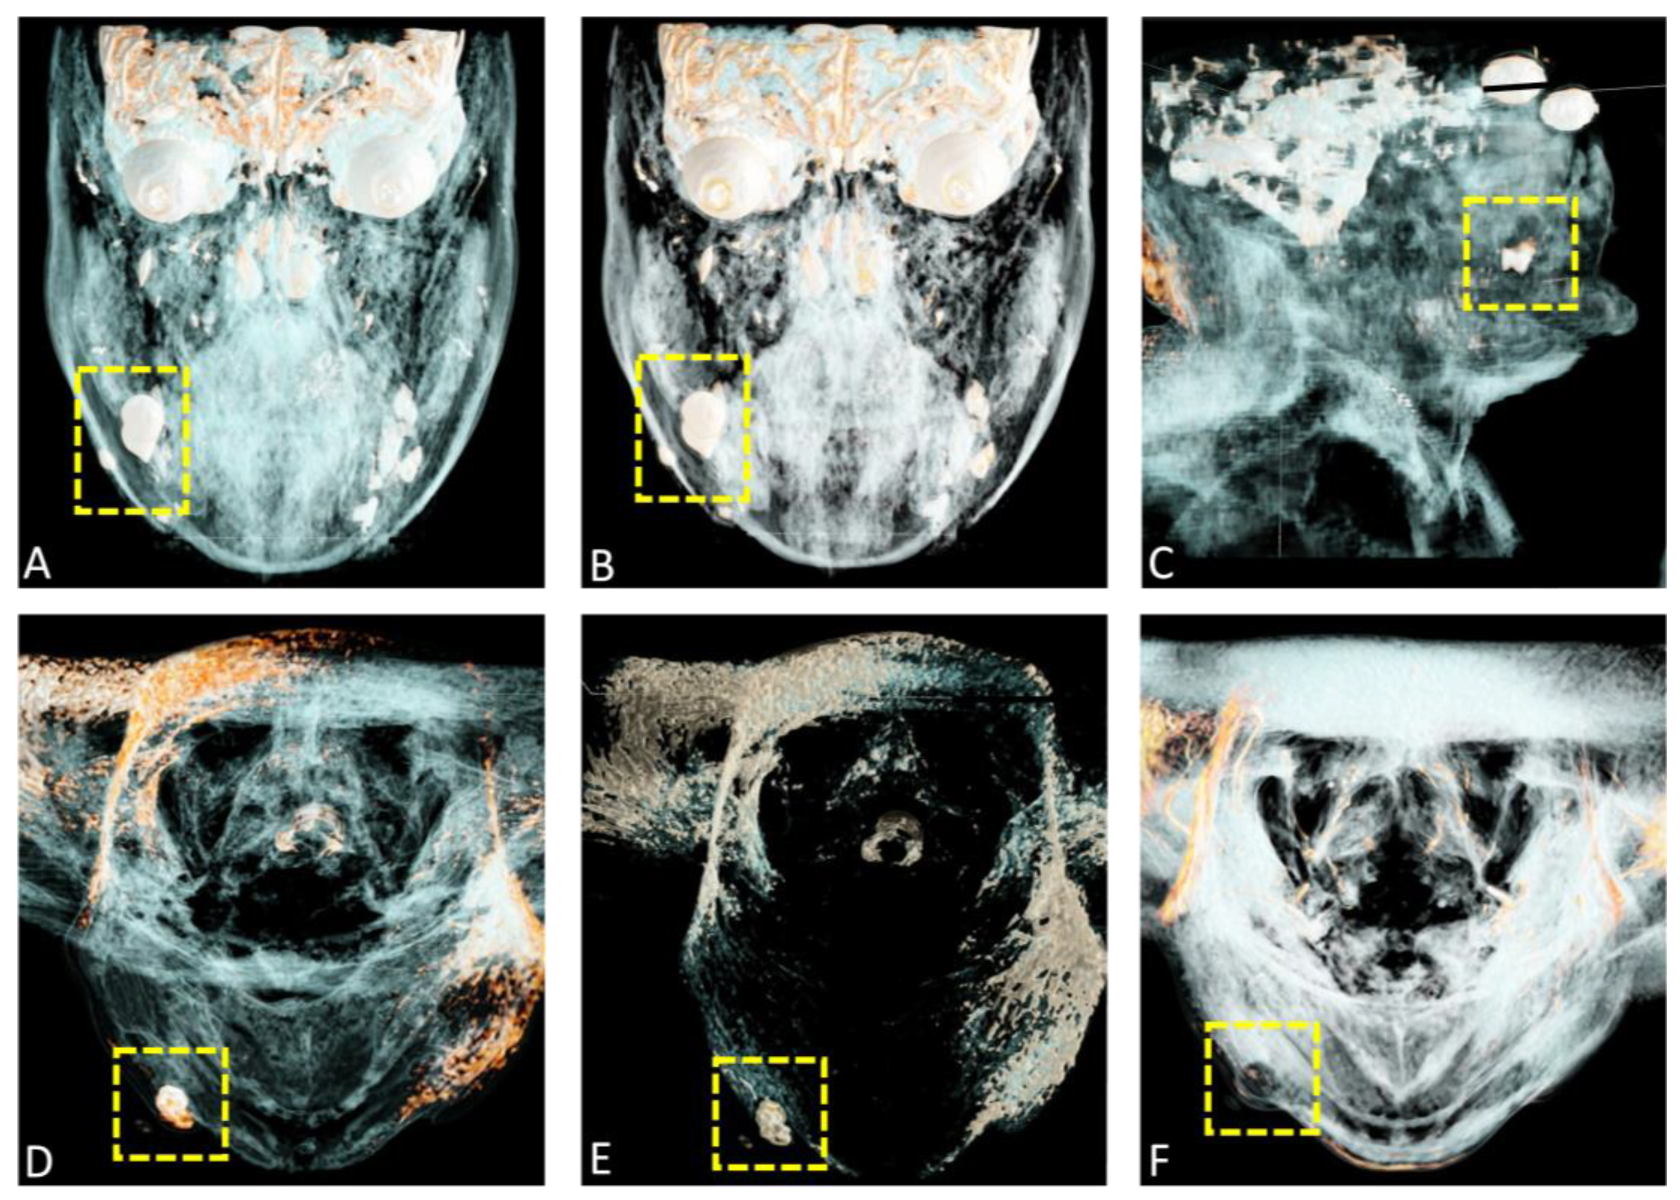

A complete surgical excision of the lesion was subsequently planned. Cinematic rendering (CR), which employs advanced algorithms to generate highly realistic three-dimensional visualizations from conventional imaging modalities like magnetic resonance imaging (MRI), enhances the representation of superficial structures by incorporating novel skin presets. Such a high level of detail is especially valuable in dermatosurgery, where precise characterization of lesions is essential for effective diagnosis and treatment planning. (A,B) present coronal views, while (C) displays a sagittal reconstruction, and (D–F) show axial preoperative CR reconstructions derived from MRI datasets. This innovative approach combines radiological diagnostics with cinematography, allowing surgeons to interact with three-dimensional volumetric models of the patient’s patho-anatomy. As a result, surgeons gain a clearer spatial understanding of lesion locations and potential surgical challenges. By employing advanced algorithms and novel skin presets, CR greatly enhances the visualization of superficial structures, offering detailed depictions of skin lesions within their anatomical context. Integrating CR into imaging workflows empowers surgeons to make informed decisions, particularly in complex anatomical regions such as the face and jaw, where precision is critical.